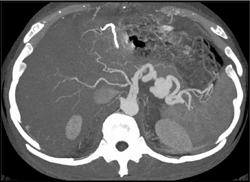

Splenic Artery Pseudoaneurysm